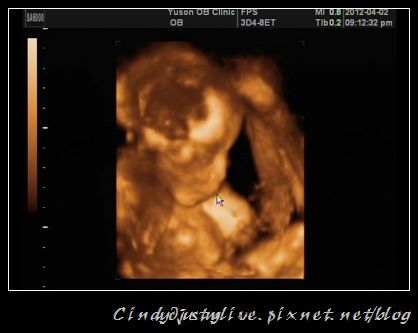

很愛沉思喔!比較清楚的4D

這次已經可以清楚看到他的樣子了,眼睛、鼻子、嘴巴、耳朵,真好奇以後他出生會是什麼樣子?

醫生又特地拍了一次他的小GG,證實是弟弟沒錯